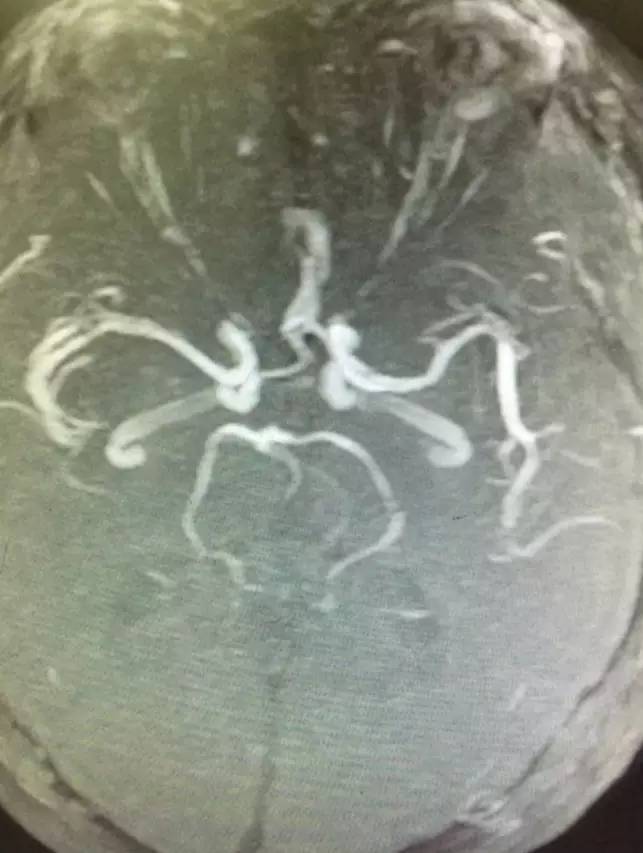

▼术后复查头颅MRI显示小脑蚓部及小脑半球有散在的梗死灶,脑干未见梗死。头颅MRA显示后循环血管通畅。